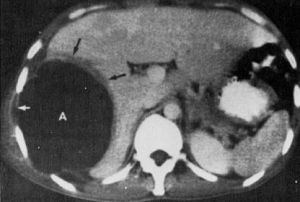

5、肝臟顯影 超聲波探查無創傷,準確方便,成為診斷肝膿腫的基本方法。膿腫所在部位顯示與膿腫大小基本一致的液平段,並或作穿刺或手術引流定位,反覆探查可觀察膿腔的進展情況。B型超聲顯像敏感性高,但與其它液

阿米巴肝膿腫 CT表現6、X線檢查 常見右側膈肌抬高,運動受限,胸膜反應或積液,肺底有雲霧狀陰影等。左葉肝膿腫時胃腸道鋇餐透視可見胃小彎受壓或十二指腸移位,側位片見右肋前內側隆起致心膈角或前膈角消失。偶爾在平片上見肝區不規則透光液-氣影,頗具特徵性。